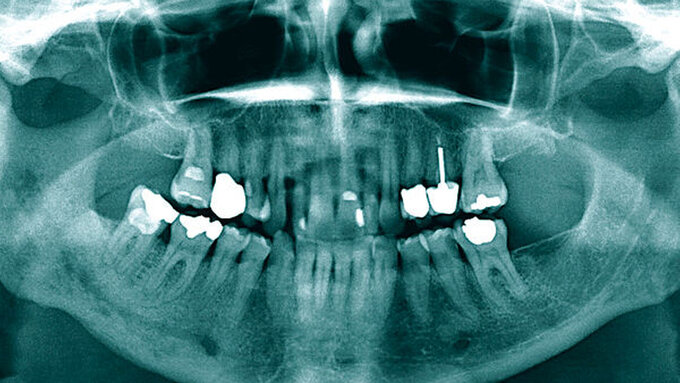

Im August 2024 stellte sich ein 50-jähriger Patient – überwiesen durch den Hauszahnarzt mit der Verdachtsdiagnose eines Sublingualabszesses – in der Notfallambulanz der Mund-, Kiefer- und Gesichtschirurgie der Universitätsmedizin Mainz vor. Anamnestisch berichtete er von erstmalig im Februar 2024 aufgetretenen Beschwerden im rechten Unterkiefer, weshalb der Zahn 45 mittels Wurzelkanalbehandlung therapiert worden sei (Abbildung 1). Die endodontische Therapie konnte laut Hauszahnarzt allerdings nie abgeschlossen werden, da der Kanal nicht vollständig trockengelegt werden konnte. Im Juli sei es dann zu einer Exazerbation der Beschwerden gekommen, einhergehend mit einer ausgeprägten Schwellung der Wange.

Nach antibiotischer Behandlung durch die orale Gabe von Clindamycin – aufgrund einer vermuteten Penicillinallergie – konnte vier Tage später der Zahn 45 extrahiert werden. Die Symptomatik persistierte jedoch und zeigte auch nach intraoraler Inzision und mehrfachem Streifenwechsel sowie Trepanation des Zahnes 46 keine Besserung (Abbildung 2). Die weitere Anamnese des Patienten war unauffällig.